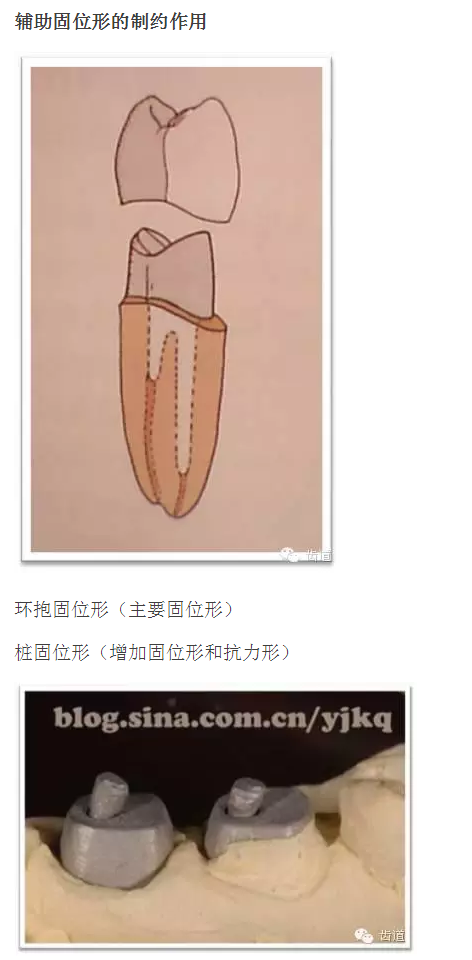

l基牙具有良好的固位形

l基牙具有良好的抗力形